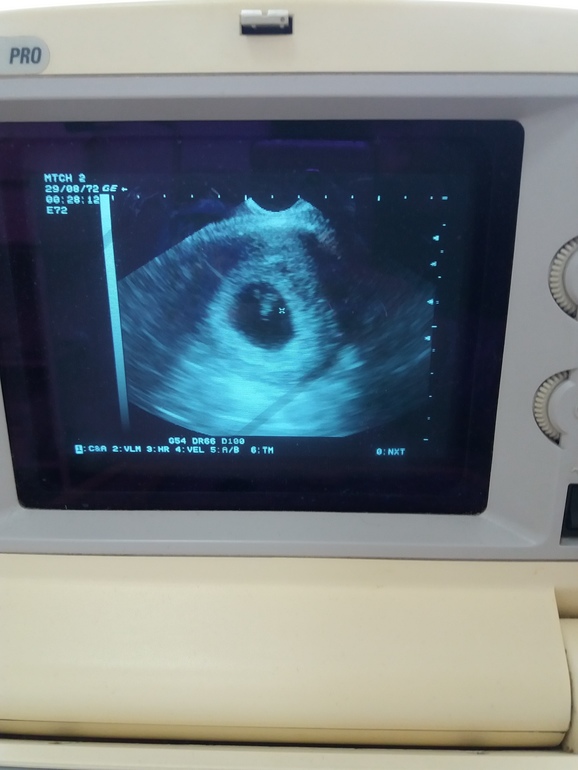

Сегодня по мес 8 недель ровно. Ходила на прием, посмотрели на нашу горошинку, сердечко бьется, с 5 недель хорошо подросли. После первой зб в 6-7 недель и отслойке во вторую бер очень боялась 7-8 неделю, но все хорошо. Буду надеяться, что и дальше все будет ок. Девочки, всем желаю такого счастья!!!

И наша первая фотка)